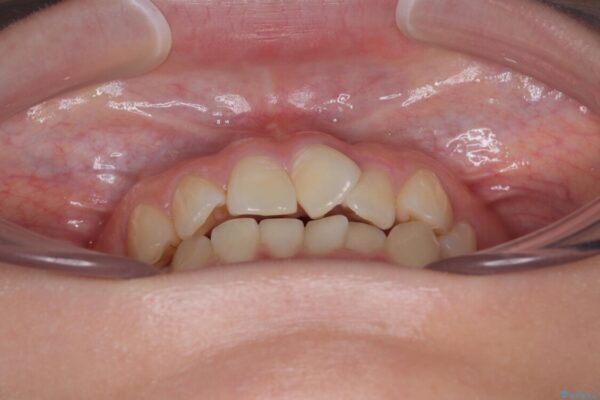

「前歯のねじれを改善したい」とのご希望で当院に来院された患者様です。

診察の結果、上下の前歯部に**叢生(そうせい/歯のガタガタ・重なり)**が認められました。

特に上の前歯にはねじれや重なりがあり、審美的にも清掃性にも影響している状態でした。

治療前

• 前歯のねじれ・ガタガタを10か月で改善!20代女性の矯正治療|クリアブラケットでむし歯になりにくい歯並びへ改善 治療前画像